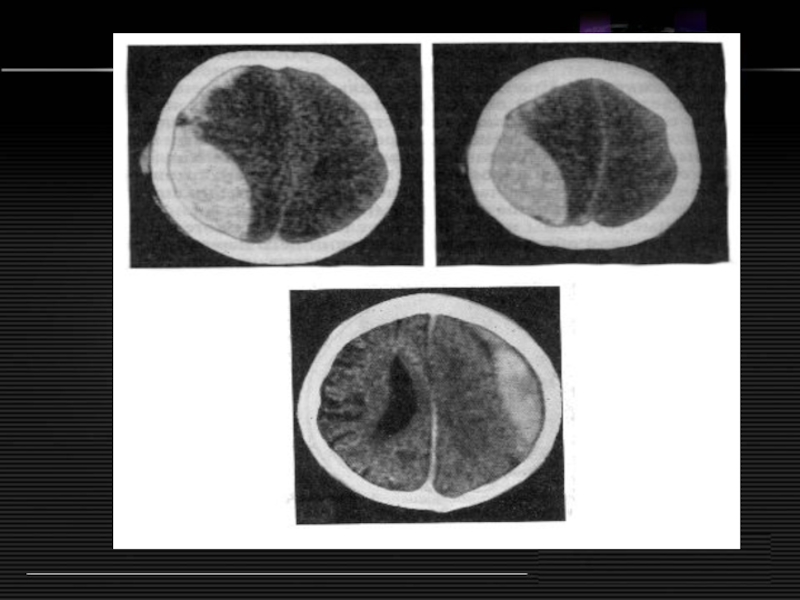

Слайд 19Ушиб головного мозга со сдавлением

Внутричерепные гематомы

Эпидуральные

16%

Субдуральные

52%

Интрацеребральные

4%

Множественные

28%

Ушиб головного мозга со сдавлением Внутричерепные гематомыЭпидуральные16%Субдуральные52%Интрацеребральные4%Множественные28%

Слайд 22Тактика экстренного диагноза

Светлый промежуток

Анизокория

Нарастающий парез конечностей

Асимметрия глубоких рефлексов

Эпиприпадки

Брадикардия

Асимметрия АД

Эхо-ЭГ, ангиография, трифинация,

КТ.

Тактика экстренного диагнозаСветлый промежутокАнизокорияНарастающий парез конечностейАсимметрия глубоких рефлексовЭпиприпадкиБрадикардияАсимметрия АДЭхо-ЭГ, ангиография, трифинация, КТ.